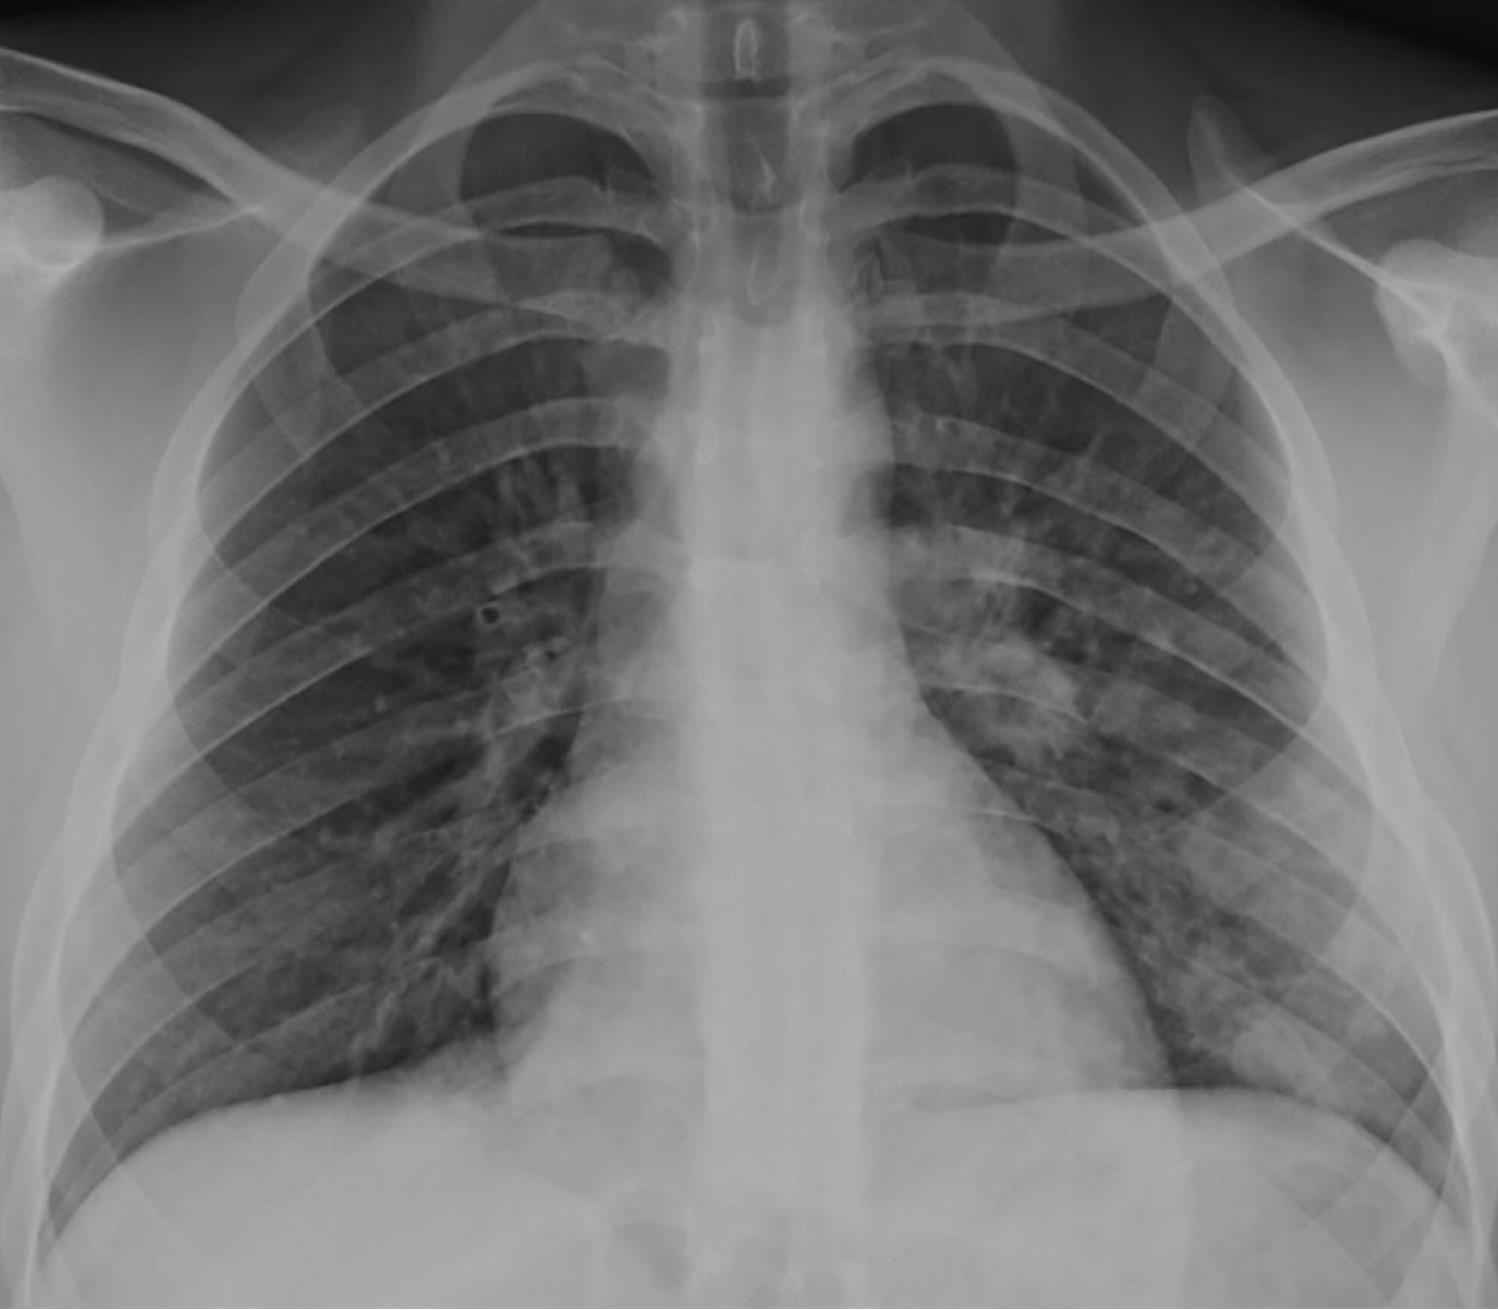

Lung Disorders CXR

COVID 19

• Patchy bilateral GGO, Consolidations or both

• Peripheral and lower lung zone predominance

• Bilateral & multifocal GGO, +/Consolidations or both

• Halo sign

• Peripheral and subpleural

• Bronchovascular thickening

• Halo sign (Early)